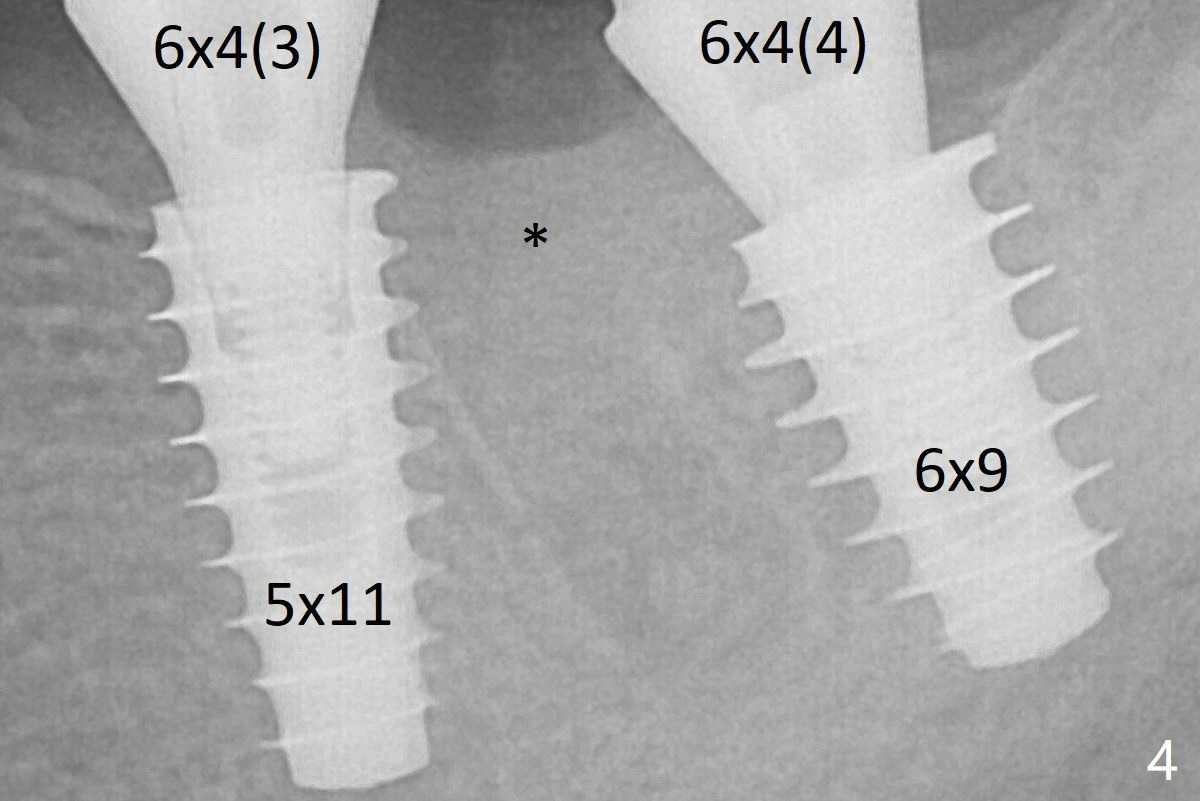

The implant at #19 could be placed more mesially (Fig.4 (*: Vera Graft)).  The implants seem to have osteointegrated 4.5 months postop (Fig.5).  The bony trabeculae form between the 2 implants crestally 12 months postop, i.e., 7 months post cementation (Fig.9).